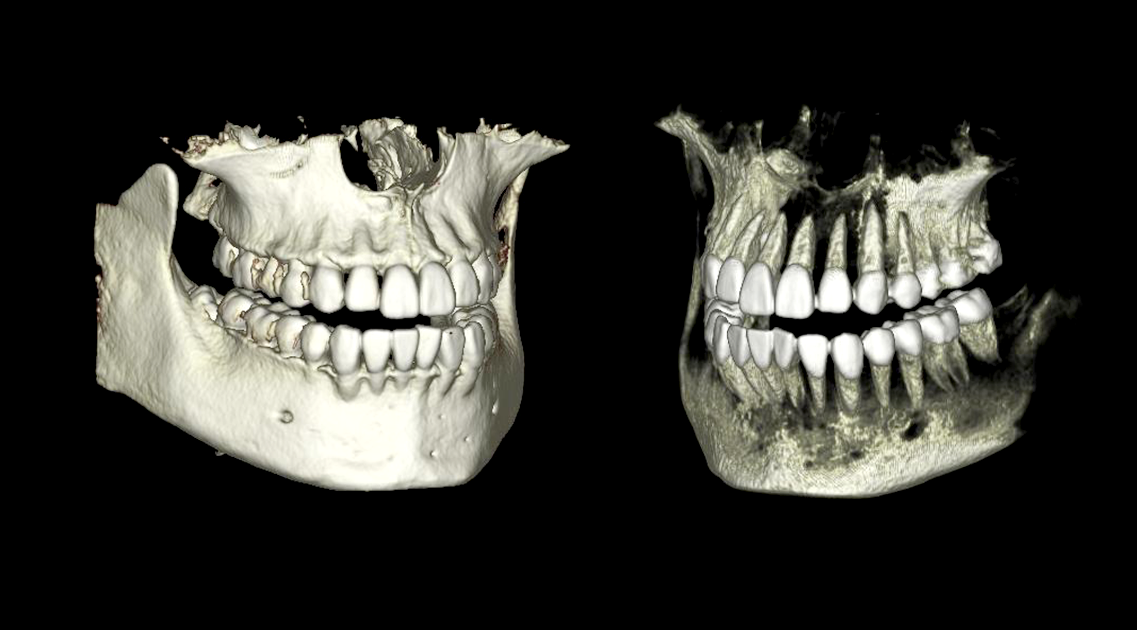

BioNaシミュレーション画像

BioNaシミュレーション画像 歯牙支持型フラップレス

歯牙支持型フラップレス